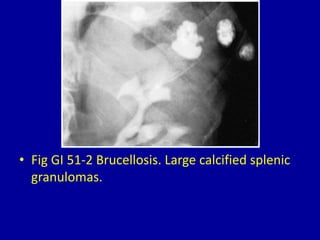

This document discusses various medical conditions that can cause calcification in the spleen that are identifiable on clinical imaging. It provides 8 figures showing examples of calcification from specific conditions, such as histoplasmosis causing multiple small calcifications, brucellosis producing a large calcified granuloma, a huge calcified nonparasitic splenic cyst, and calcification of the splenic artery or from a splenic artery aneurysm. Sickle cell anemia is also noted as potentially increasing splenic density on imaging.